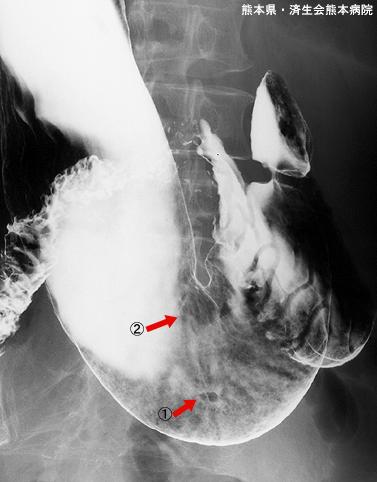

건강검진에서 발견된 조기위암과 GIST (증례제시:쿠마모토현, 사이세이카이 쿠마모토병원, Dr. 요시타)

악성 상피성종양/선암

위(부위)/위각

X-P

0형(표재형)/IIc형(IIc)

1~9

sm